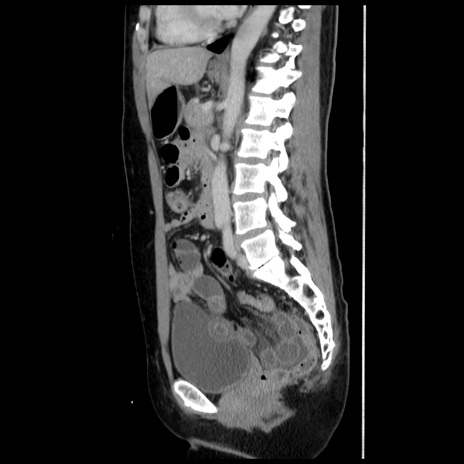

症例10(矢状断像)

【症例】 50歳代女性

【主訴】 腹痛

【現病歴】前日生レバーを食べた。今朝に排便あり。 昼前に突然発症の腹痛を生じ、当院救急外来を受診した。

【既往歴】 子宮筋腫にてで子宮全摘後

【身体所見】 意識清明、腹部:平坦、軟、下腹部やや左を中心に圧痛・反跳痛あり、筋性防御あり

【データ】WBC 7800、CRP 0.07